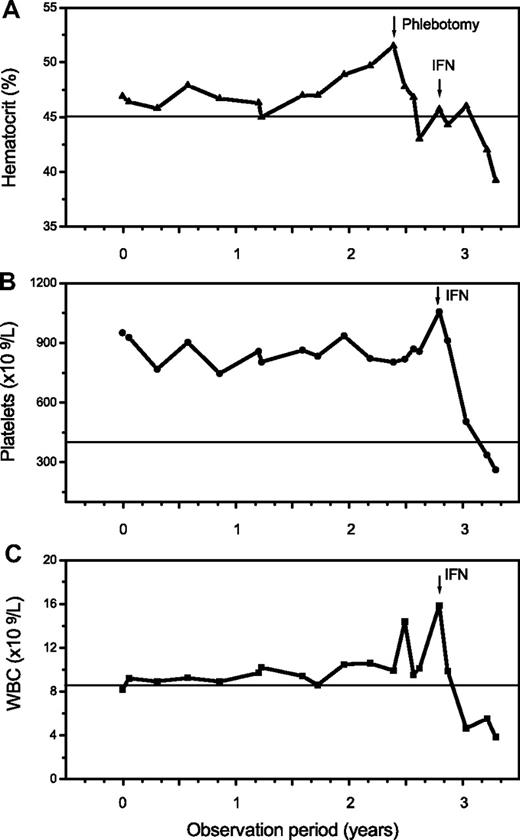

The additional small group of 12 patients with overlapping morphologic as well as clinical features of ET/PV displayed a sustained thrombocythemia (685 × 109/L) and borderline increased hemoglobin (male, 15.8 g/dL; female, 15.3 g/dL) values. Contrasting the other entities, this cohort had a serum erythropoietin level at the lower range (1.2-4.8 U/L), and all showed a positive JAK2 mutation status. Consistent with histologic BM features, an overlapping morphology between ET and PV was noted (Figure 4). Accordingly, clinical findings and particularly follow-up were suspicious in this hybrid group for occult-initial (prepolycythemic) PV mimicking ET at presentation, at least in a few patients. During the observation period, 4 patients evolved into manifest PV (Figure 5). However, most of these cases should be diagnosed as presenting with MPN-U.

Follow-up in a 46-year-old patient clinically presenting as ET with a platelet count of 951 × 109/L, a hemoglobin/hematocrit value at the upper limit, a positive JAK2 mutation status, and an erythropoietin level of 2.0 U/L. There was an increase of the hematocrit and white blood cells (WBC) starting after more than 2 years of observation with manifestation of overt PV requiring treatment with interferon (IFN).

Follow-up in a 46-year-old patient clinically presenting as ET with a platelet count of 951 × 109/L, a hemoglobin/hematocrit value at the upper limit, a positive JAK2 mutation status, and an erythropoietin level of 2.0 U/L. There was an increase of the hematocrit and white blood cells (WBC) starting after more than 2 years of observation with manifestation of overt PV requiring treatment with interferon (IFN).